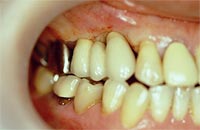

「入れ歯が合わなくて…」「食べ物がうまく噛めない」「発音や発声がうまくできない」「入れ歯を使うと痛みや異物感を感じる」「ブリッジのために健康な歯を削りたくない」

このような「歯」や「入れ歯」のお悩みをお持ちの方に「インプラント治療」をおすすめします。